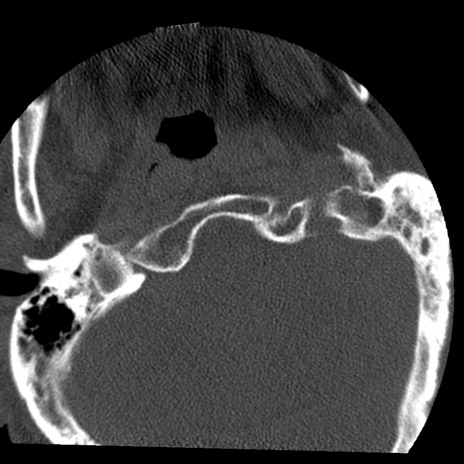

症例50 頚椎CT(横断像)

冠状断像